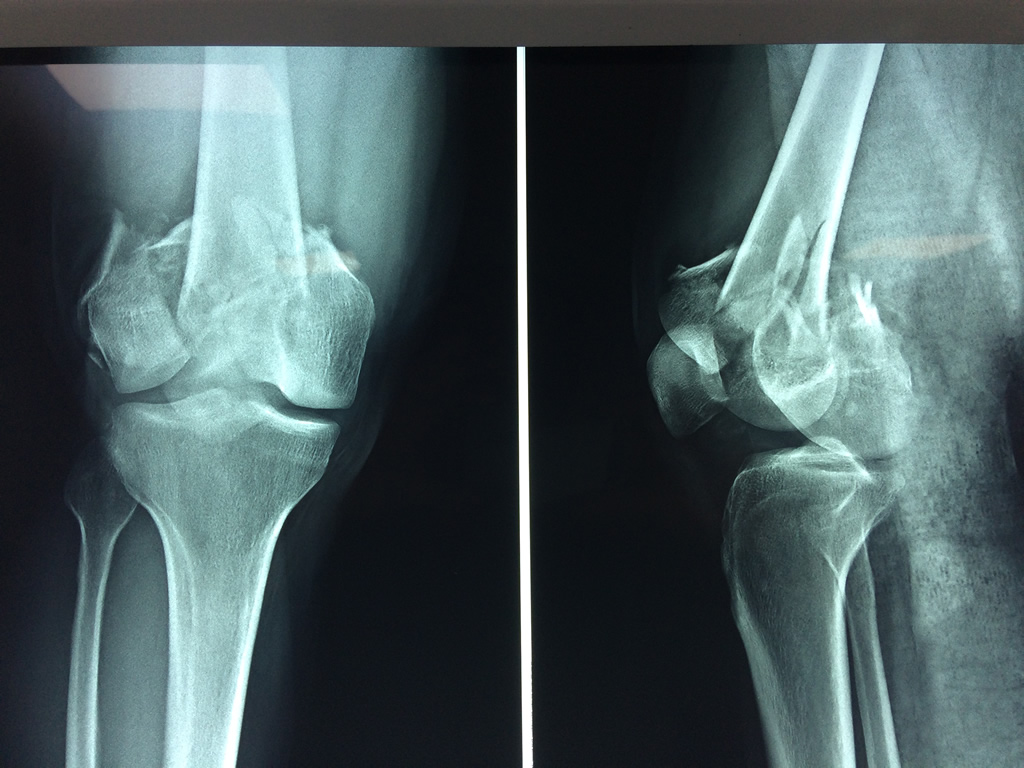

Cirugías de Rodillas

El fémur es el hueso del muslo, el segundo segmento del miembro inferior. Es el hueso más largo, fuerte y voluminoso del cuerpo humano.